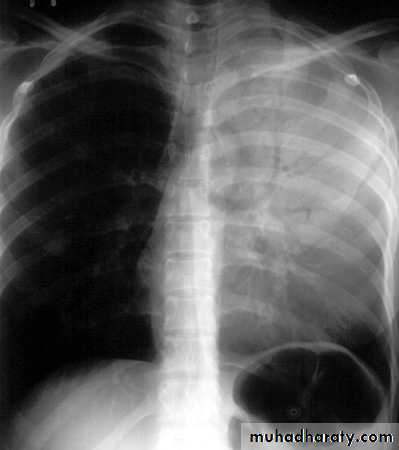

Massive pleural effusion